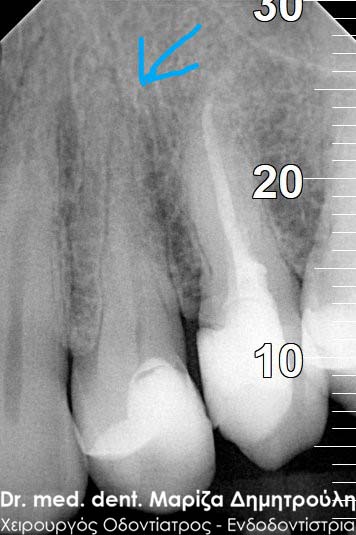

Η ασθενής προσήλθε με έντονο πόνο στο ιατρείο και είχε λάβει τις προηγούμενες μέρες αντιβίωση, εφόσον στην άνω αριστερή πλευρά της είχε οίδημα. Μετά την κλινική εξέταση διαπιστώθηκε η ύπαρξη ενός συριγγίου υπερώια μεταξύ των δύο άνω αριστερών γομφίων. Πραγματοποιήθηκε ακτινογραφία με την τοποθέτηση ενός κώνου γουταπέρκας για τη διάγνωση του υπαίτιου δοντιού, που είχε προκαλέσει την εμφάνιση του συριγγίου. Σύμφωνα με όσα αποκάλυψαν η κλινική και ακτινογραφική εξέταση ακολούθησε η έναρξη απονεύρωσης στο δεύτερο άνω αριστερό γομφίο, δεδομένου οτι είχε ένα βαθύ λευκό σφράγισμα ρητίνης που εκτεινόταν στο ύψος του νεύρου του δοντιού. Το δόντι είχε έντονα συμπτώματα πόνου κατά την επίκρουσή του.

Μετά την ολοκλήρωση της απονεύρωσης στο δεύτερο άνω αριστερό γομφίο το δόντι είναι ασυμπτωματικό. Η αποκατάσταση του δοντιού πραγματοποιήθηκε με λευκό σφράγισμα ρητίνης, εφόσον το έλλειμμα των οδοντικών ιστών ήταν μικρό και δε χρειαζόταν η προστασία του δοντιού με θήκη / στεφάνη δοντιού.

Σε δεύτερη φάση θα ακολουθήσει η επανάληψη απονεύρωσης στον πρώτο άνω αριστερό γομφίο, καθώς η απονεύρωση του δεν καλύπτει όλο το μήκος των ριζών του δοντιού και το δόντι μετά το πέρας της ενδοδοντικής θεραπείας συνεχίζει να πονά.

ΠΡΙΝ